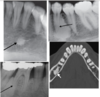

Is this Globulomaxillary Cyst , lateral granuloma or OKC?

~ it is kind of a teardrop or pear shaped size

~Little less well differentiated in this particular instance but again unilocular radiolucency between the roots of two teeth

This one ended up being an OKC